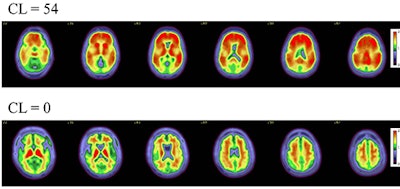

Axial color scales images of two brains show examples of an amyloid positive scan with a higher centiloid (CL) number and more red colors compared to a normal scan with normal background binding of the amyloid tracer signifying no amyloid plaques.Axial color scales images of two brains show examples of an amyloid positive scan with a higher centiloid (CL) number and more red colors compared to a normal scan with normal background binding of the amyloid tracer signifying no amyloid plaques.Image and caption courtesy of RSNA.